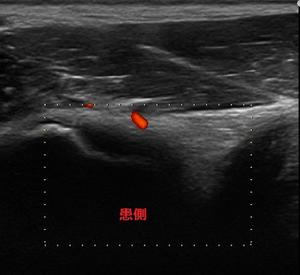

いつもの通りしっかり問診、触診、理学検査後にエコー検査。

下前腸骨棘健側.jpg下前腸骨棘患側.jpg結果、下前腸骨棘付近、大腿直筋起始部の炎症と判明。